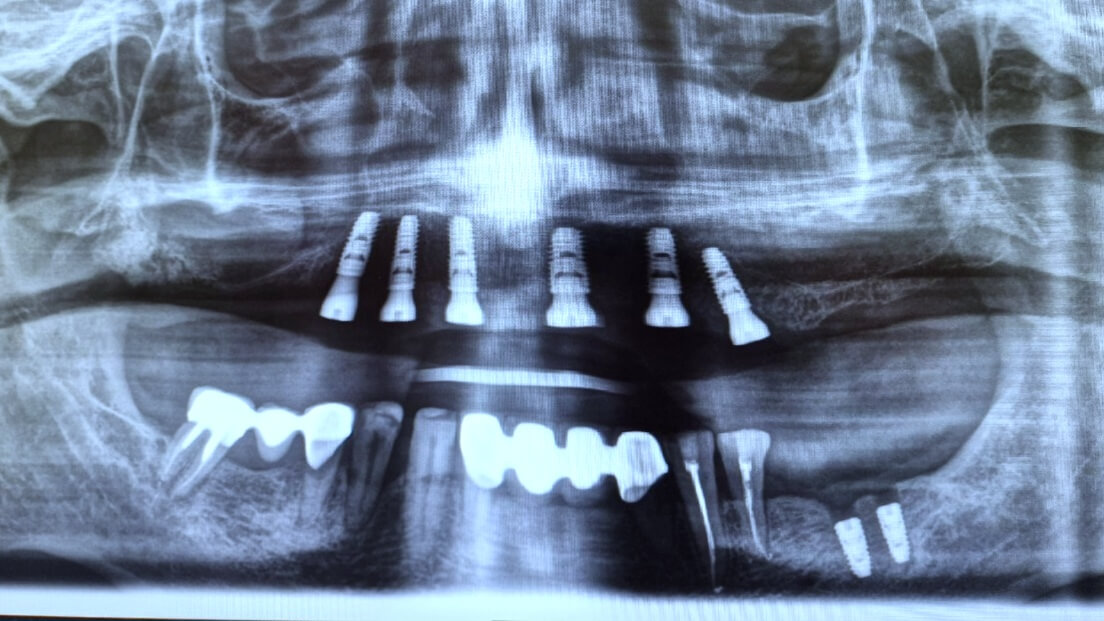

Імплантація зубів All-on-6, Все-на-шести

Вихідна ситуація: скарги пацієнта на повну відсутність зубів на верхній щелепі та часткову втрату на нижній. Це призводило до труднощів у жуванні, порушення дикції та зниження якості життя. Після детального обстеження та консультації було прийнято рішення провести протезування за методикою "все на шість" на верхній щелепі. Ця технологія передбачає встановлення шести імплантатів, на яких фіксується незнімний протез. Це дозволяє відновити повну функціональність та естетику зубного ряду. На цей час пацієнт перебуває на етапі підготовки до імплантації. Метою є не тільки відновлення функціональності, але й покращення естетичного вигляду, що позитивно вплине на самооцінку та соціальну активність пацієнта.